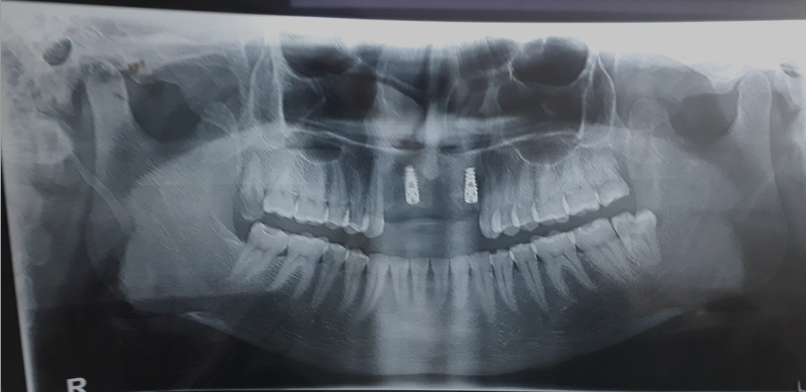

Acknowledging, patients medical condition various prosthetic options including Removal Partial denture after extracting of remaining Non-vial tooth/root structure, Fixed partial denture excluding Implant, Basal Implant supported fixed partial denture. The patient wishes to have any procedure that is less traumatic, in fewer sitting and fixed option. Thus, After through evaluation we opted to replace missing teeth with Basal implant supported Fixed partial denture. And even preoperative radiograph suggested sound bone and sufficient space for placement of a long implant with bicortical engagement.

The use of single piece immediate implant (BSC) in the newly extracted area provide better attachment for a basal implant. A flapless immediate implant procedure was used for placing implants. Considering the demands and needs of the patients, It was decided to place a 3.5 mm diameter and 21 mm insertion-length Bicortical screw implant in the edentulous space of maxillary right central and left lateral incisor.([Figure 1])

Impression of maxillary and mandibular ach was recorded using addition silicon impression material and was then transferred to master cast. Further, it was send to dental lab for the preparation of Fixed bridge and ceramic prosthesis. Patient was asked to visit after 10 days for permanent crown and bridge prosthesis. Moreover, Subject was kept in antibiotics therapy with analgesic For 10 days. (Amoxicillin 500mg + clavulanic acid 125 mg BD, Metronidazole 400 mg BD and Aceclofenac 100mg + Paracetamol 325mg + Serratiopeptidase 15mg BD). On 10th day areas was completely healed and OPG radiographs show no abnormalities Or anything periodontal disease or complications due to implant placement. Hence, patient was ready for final fixed prosthesis.[Figure 5]